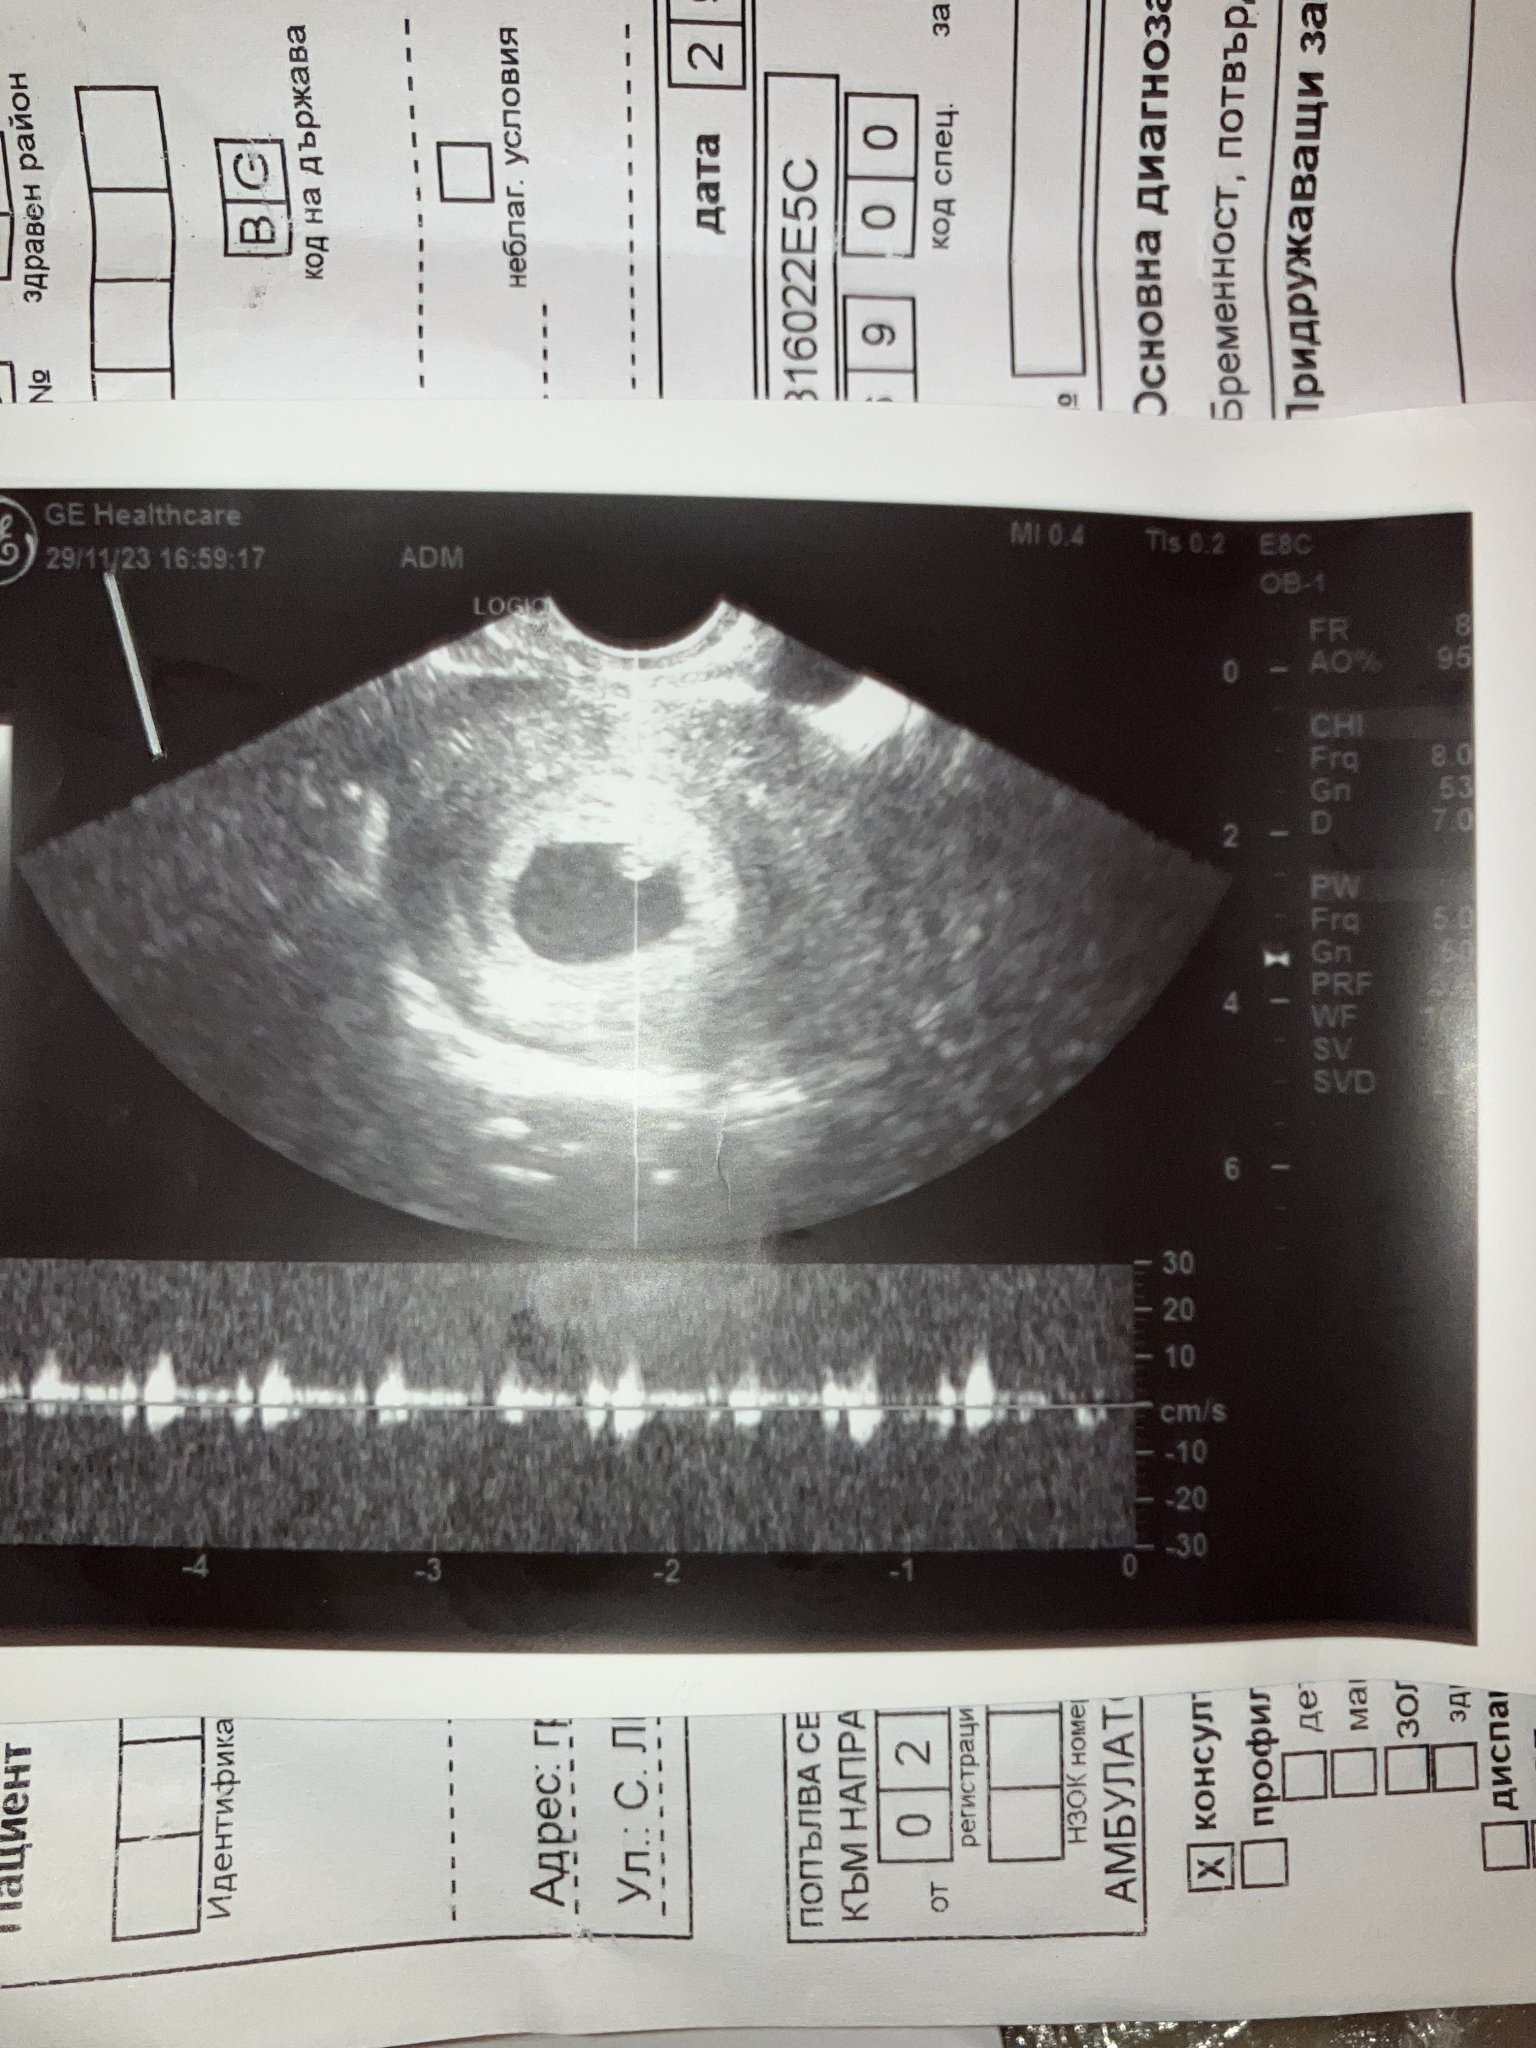

Здравейте, това е ехографа след прегледа ми днес. Понеже съм с нередовен цикъл и не знам точно кога съм забременяла. Според мен трябва да съм около 5-6 г.с, но според ехографа преди две седмици бях в 5г.с а днес в 7г.с. Гледаха ме с коремен ехограф, но според доктора за седмиците който излизат на ехографа все още няма ембрион и ме викна отново другата седмица в четвъртък. Според вас има ли нещо притеснително?

Това са снимките от двата ехографа и двата са коремни, в нашия грах нямаме вгинални.